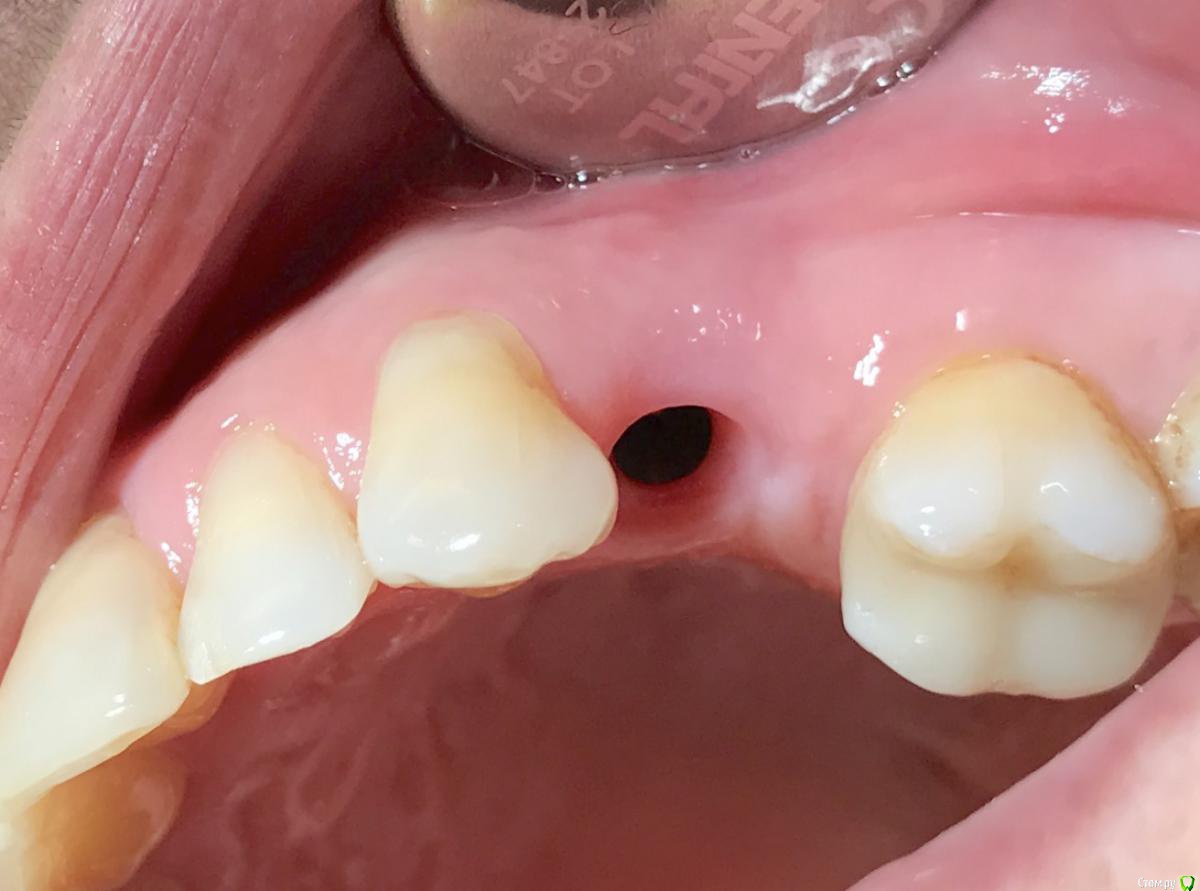

колесников Опубликовано 25 февраля, 2017 Поделиться Опубликовано 25 февраля, 2017 Здравствуйте коллеги! Представляю вашему вниманию этот клинический случай.В ноябре 2016 обратилась пациентка с жалобами на выпадение ортопедической конструкции в обл 24. Объективно: корни 24 не состоятельны. ,на десневом крае в проекции 24 свищевой ход с гнойным отделяемым.На КТ резорбция вестибулярной компактной пластинки и деструкция костной ткани в области щёчного корня.Приняв во внимание крайне негативное отношение пациентки к каким бы то ни было хирургическим вмешательствам и высоким эстетическим требованиям,было решено пойти на немедленную имплантацию .Снимки в день вмешательства,через 7,14 дней и 3мес.Имплант Astra tech profile 4.5х11мм. Сст с бугра вестибулярно. Вместо графта губки Коллапола (не вспомню причину,либо не было в наличии,либо отказ пациента). 15 Ссылка на комментарий

колесников Опубликовано 26 февраля, 2017 Автор Поделиться Опубликовано 26 февраля, 2017 Да,можно было ещё на 1мм притопить,и конечно графт вестибулярно оставить,но это стало понятно только сейчас. При постановке имплант был заглублен на 3 мм, посчитал что этого достаточно, но резорбция случилась больше планируемой. Первоначально планировалась нагрузка через 5 сут ,но ортопед позднее отказался от этой идеи. Думал заменить фдм на зебру,но пациентка пропала на 3 мес... Как получилось,так получилось. Торк был 35н/см,как обычно на астре. Ссылка на комментарий